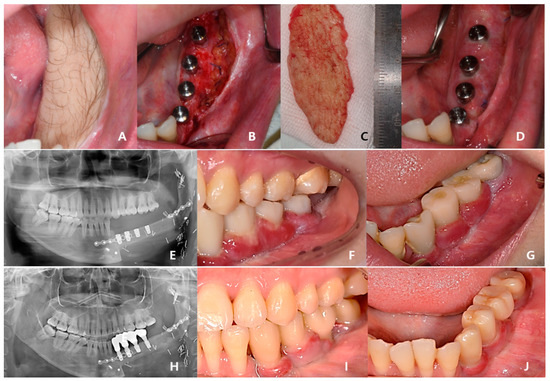

A 24-year-old female patient was identified with osteosarcoma of the left mandible body and referred to Kyung Hee University Dental Hospital. Preoperative enhanced computed tomography (CT) and enhanced magnetic resonance imaging (MRI) confirmed a tumor of approximately 2.5 cm that had eroded the buccal cortical bone and was bulging out (Figure 1). A wide excision, including segmental mandibulectomy, was planned with a sufficient safety margin. The fibula free flap was considered first since a bony free flap containing soft tissue was required to repair the lining oral mucosa and mandible.

Figure 1. Preoperative enhanced CT (1.0 mm slice) scan showing the malignant tumor eroded the left buccal cortical bone and bulged. (A) axial view; (B) frontal view (red lines outline the lesion and surrounding tissue).